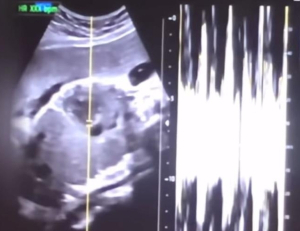

- '36주 낙태' 병원장 등 구속기소…제왕절개 후 냉동고 넣어 살해

- ▲ 낙태한 산모의 유튜브 동영상에서 캡쳐한 초음파 사진과 심박 그래프 (사진=서울중앙지검 제공)[e-뉴스 25=백지나 기자] 신생아와 다름없는 36주 차 태아를 ...